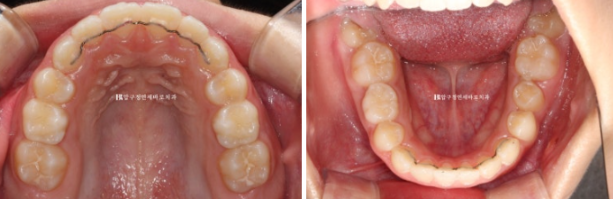

치아 나올 공간이 부족한 것은 아니여도 소량의 악궁확장을 통해 앞니 돌출을 어느정도 해소하기로 했습니다.

무턱 주걱턱 비대칭 등의 골격적 문제는 없었어서 바로 인비절라인 퍼스트 치료에 들어갔고 첫 장치를 끼기 시작한것은 23년 11월입니다.

어린이 교정이지만 결과가 성인교정 결과에 준하는 만큼 철사 유지장치도 성인교정에 준하게 들어갑니다.

교정 종료 시점 유치는 아직 3개가 남았습니다.